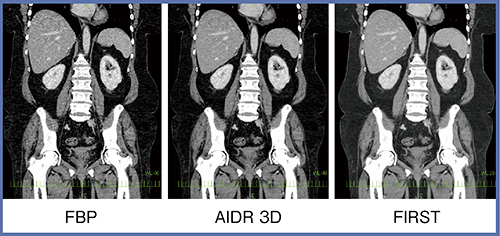

症例7(50歳代,女性)は,BMI38.5の高度肥満で,胃の縮小手術のために受診した(図8)。高度肥満の場合,特に肝臓の上方辺りはストリークアーチファクトが強く出て診断が困難なことも多いが,AIDR 3D,さらにFIRSTでは,ストリークアーチファクトが強力に抑制されることがわかる。

図8 症例7:高度肥満(50歳代,女性)